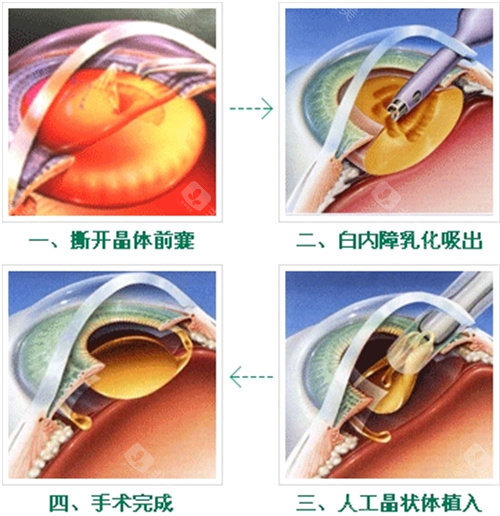

白内障正规开展了多种白内障手术,包括超声乳化白内障吸除术等,手术技术成熟,术后结果良好。

此外,科室还开展了一些潮流的眼科手术技术,如飞秒激光辅助白内障手术等,大大提高了手术的可靠性和有效性。